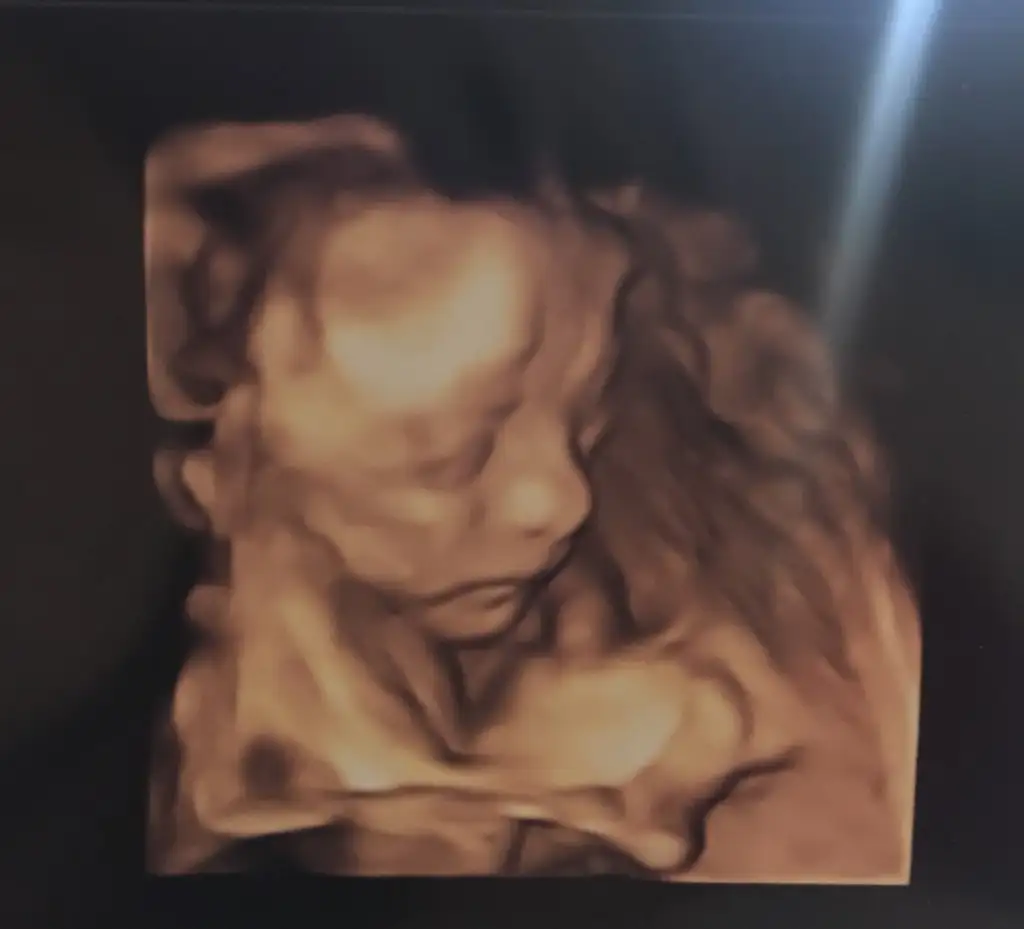

Biz detaylıdan çıktık çok şükür bebişin sağlığı yerinde, koca burunlu erkeğe benzeyen bi kızım olacak galiba